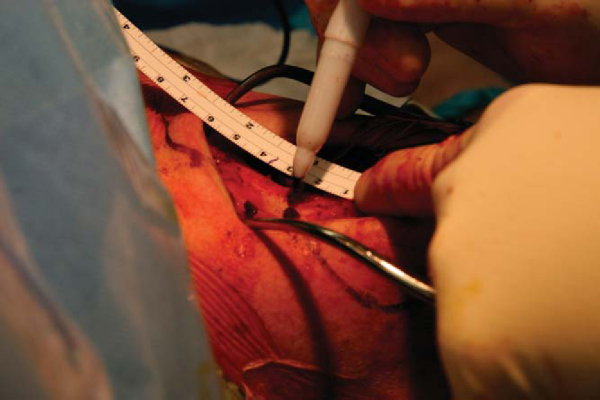

A No. 10 blade scalpel is used to make a 6-cm longitudinal incision, centered over or slightly medial to the coracoid. Medial and lateral skin flaps are elevated with a needle-tipped bovie. Gelpi retractors assist with exposure. A transverse incision is made along the midaxis of the clavicle extending into the acromioclavicular joint. Full-thickness flaps of the superior acromioclavicular joint capsule are elevated superiorly and inferiorly with a needle-tipped bovie. The anterior and posterior portion of the distal clavicle is completely exposed (

Fig. 28-3

). If acromioclavicular joint arthrosis is present, 5 mm of distal clavicle is resected. Many surgeons perform a distal clavicle resection (

Fig. 28-4

). However, there is tremendous variability in the acromioclavicular joint, and there seems to be tremendous stability from an intact acromioclavicular joint. For that reason, I believe that it may be advantageous to preserve the distal clavicle and have done so in select patients.